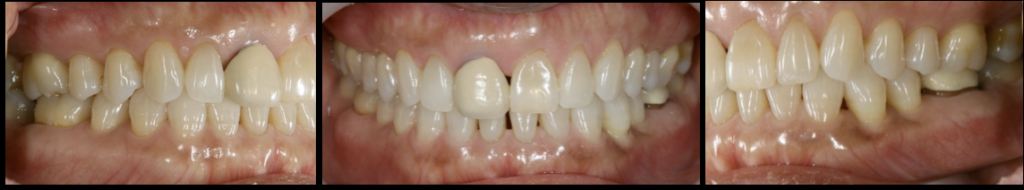

- 上顎右側前歯にインプラントを1本抜歯即時に埋入し、

- オールセラミックにて被せ物を行なった。

- 下顎左側臼歯に1本のインプラントを待時に埋入し、オールセラミッククランにて被せ物を行なった。

治療結果

- 審美的な仕上がりで、患者自身も満足した。15年経過し良好である。

現在は2〜3ヶ月おきのメインテナンス中である。